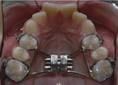

Hamilelikte takma diş damak yarası yaşadım ve gerçekten rahatsız ediciydi. Özellikle ağız hijyenine dikkat etmediğimde kanama ve hassasiyet arttı. Doktorum düzenli kontrollerin önemli olduğunu vurguladı. Umarım bu durumu yaşayan diğer hamileler de dikkatli olur ve zamanında önlem alır.

Geçmiş Olsun Kongurtay, yaşadığınız bu durumun ne kadar rahatsız edici olabileceğini anlıyorum. Hamilelik döneminde vücut birçok değişim geçiriyor ve ağız sağlığı da bunlardan biri. Ağız hijyenine dikkat etmek gerçekten çok önemli, çünkü bu tür yaralar hem rahatsızlık verebilir hem de daha ciddi sorunlara yol açabilir.

Düzenli Kontroller doktorunuzun da belirttiği gibi, düzenli kontroller hamilelik sürecinin sağlıklı geçmesi için kritik. Diğer hamilelerin de bu konuda bilinçlenmesi ve gereken önlemleri alması, hem kendi sağlıkları hem de bebekleri için oldukça önemli. Umarım, sizin gibi bu durumu yaşayanlar da bu süreçte daha dikkatli olurlar. Sağlıklı bir hamilelik dönemi geçirmenizi dilerim.